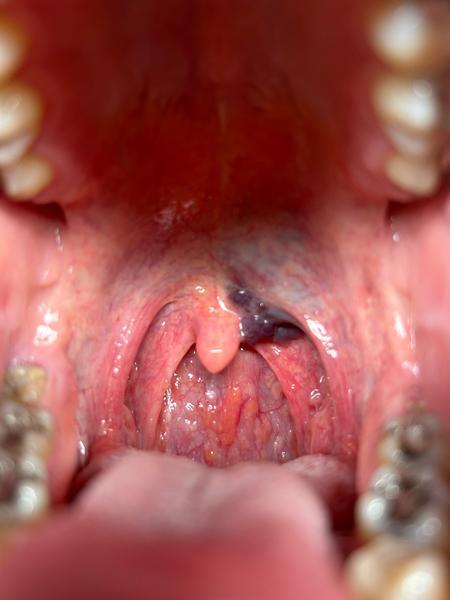

Dobrý deň, prosím vás vedeli by ste mi poradiť? V hrdle mám krvnú zrazeninou už niekoľko rokov pri hltane, veľmi pomaly sa zväčšuje každý rok, do takéhoto stavu narástla počas 20tich rokov. Bol som na kontrolu na ORL, a povedali mi že nádor to nieje, ale prikladám aj fotku hrdla, mám sa obávať toho najhoršieho? Krvný obraz rakovinu nepotvrdil….dala by sa krvná zrazenia odstrániť? Da sa to operovať? V minulosti som mal vždy problémy s mandlami, a stena hrdla tiež vyzerá stále ako zapálená…. Prosím o radu akého odborníka by som mal navštíviť, aby som to mohol riešiť. Dakujem